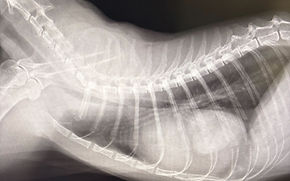

横隔膜ヘルニア